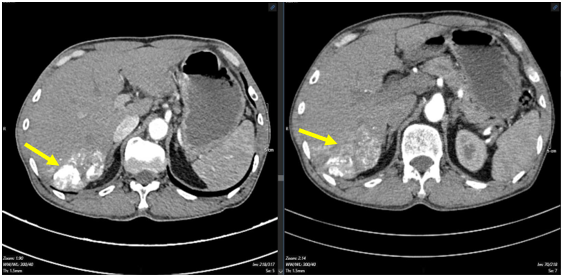

– Tháng 3/2025: Hình ảnh u phân thùy sau gan phải, kích thước 28x38mm, hiện còn tăng sinh mạch (Sau TACE lần 3). Sỏi túi mật. Sỏi thận hai bên.

Hình 3: U gan sau nút mạch lần 3, vào tháng 03/2025 (bên trái, mũi tên vàng) so với trước khi nút mạch lần 3 vào tháng 02/2025 (bên phải, mũi tên vàng)